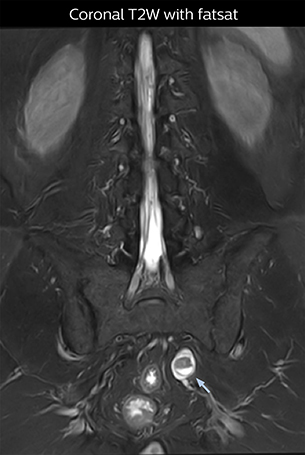

“In such case, we would then browse through axial T2-weighted MR images slice by slice and mentally reconstruct the actual situation based on both radiculography and MRI. Fortunately, NerveVIEW can now very well show nerve courses and presence of nerve compression or edema in one single image series.” “We have often seen NerveVIEW directly depict details of the nerve compression that were not observed by radiculography. Therefore, we think that with NerveVIEW we can reduce the number of invasive examinations, especially for some patients with lumbar plexus symptoms.”

“Before NerveVIEW, diagnosis by MRI alone was sometimes difficult, unless there was a strong suspicion based on clinical symptoms,” says Shoji Yabuki, MD, DMSc, Orthopedic surgeon at Fukushima Medical University School of Medicine. “This is why we routinely perform selective lumbosacral radiculography (nerve root block) and x-ray in such cases. However, radiculography can only depict nerves as far as the contrast agent reaches. When a nerve is distorted by compression, the contrast agent will not pass through this compressed area, preventing us from evaluating the full nerve compression.”

“For example, in sagittal images, when the presence of fat is observed in the intervertebral foramen, it suggests that there is a margin around the nerve. Similarly, the absence of fat indicates that the nerve is being compressed. So, we used to deduce nerve compression indirectly. With NerveVIEW, however, we can observe the condition of the nerves directly, regardless of the presence or absence of fat. We always prefer such direct observation of anatomy over having to make an inference about it.”

“Although symptoms of typical disc herniation and atypical hernia are very similar, the actual site of herniation is different. It is therefore important to characterize the nerve’s condition both inside and outside of the intervertebral foramina. “Conversely, if we see no abnormality in NerveVIEW, we can assume at least that there is no severe condition that requires surgery. Like this, it can help us avoid unnecessary surgery. NerveVIEW can have a tremendous impact in this way.”

“NerveVIEW is really useful for those cases where a nerve disorder is strongly suspected based on the clinical examination but our regular MRI images do not show any findings. These atypical herniations and spinal canal stenosis, occurring in 5% to 15% of the total lumbar herniation/stenosis cases are our main target when using NerveVIEW,” says Dr. Yabuki.